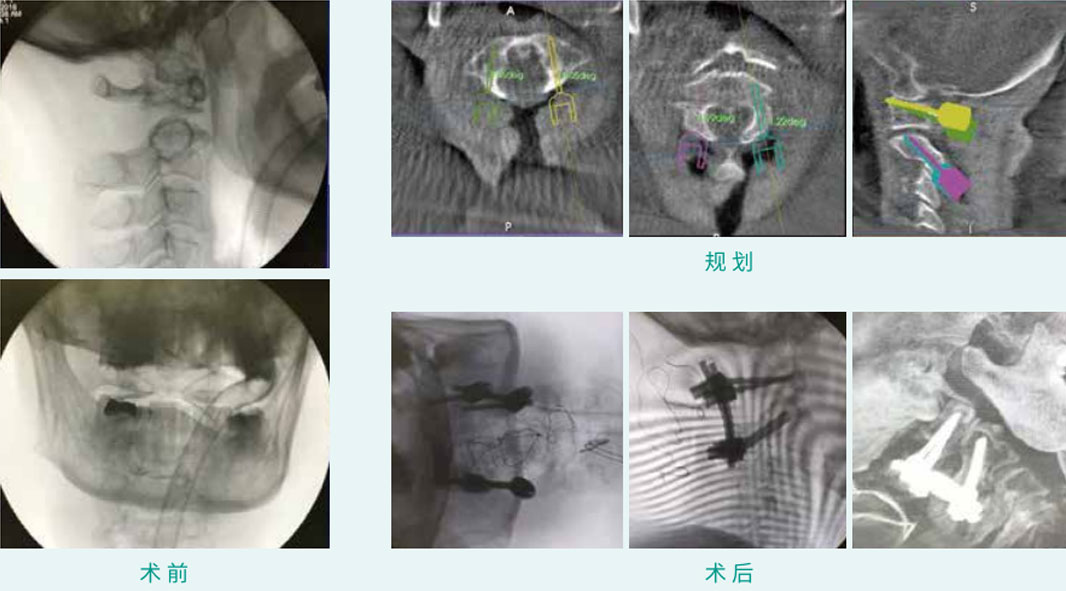

天玑? 辅助寰枢椎椎弓根螺钉内牢靠术

基本情形:患者女,65岁,寰枢椎脱位

机械人累积用时:35分钟

植入物:4枚椎弓根螺钉

病例泉源:广东省中医院 林定坤 陈博来 李永津